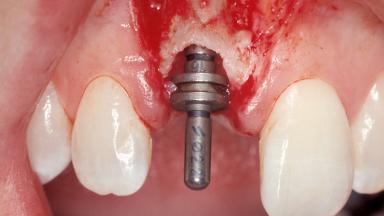

Immediate Placement of an Implant in a Maxillary Right Central Incisor Site

A 30-year-old female patient was referred to the office for the treatment of tooth 11. Her chief concern at the initial visit was to inquire, “Why is my tooth pink?” Upon clinical examination, it was determined that tooth 11 had a previous history of trauma and that the clinical crown had become noticeably pink in color as a result of internal resorption. This diagnosis was confirmed radiographically, indicating a large radiolucency involving the central and distal portions of the clinical crown. It was determined that restoration of this tooth was not possible, and that extraction was indicated. The presence of a mid-line diastema, which the patient wanted to reproduce, directed the treatment plan for tooth replacement utilizing a dental implant.

Type of Implants One-Piece|Reduced-Diameter

Placement Protocol Immediate implant placement

Tooth Site Maxillary incisor or canine

Bone Volume Sufficient, with intact walls